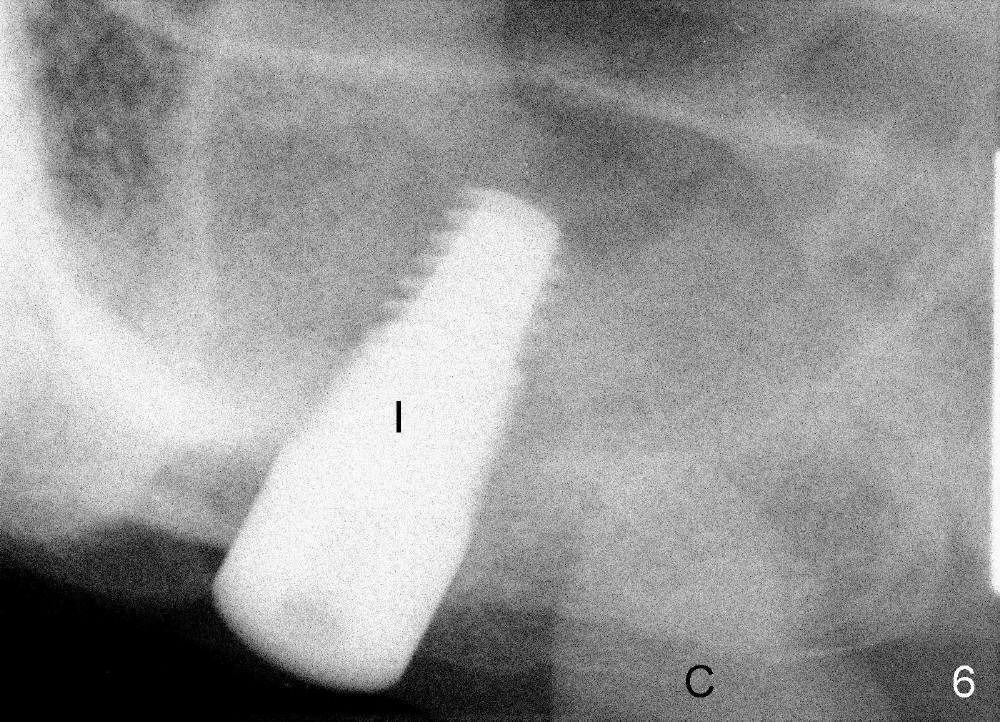

首先在左上五,六号牙之间切断牙桥(图一:黑线),七号基牙比五号松,前者鄂侧牙周袋深,所以对七号牙大刀阔斧,不幸远中颊侧根断裂(图三:离体牙颊侧观;MB:近中颊侧根),可能因为根弯曲,或者死髓牙。图四是离体牙近中观:把断根(远中颊侧根:DB)插回原处,试图把种植体植入三个牙根之间中隔(septum),不过最后种植体主要进入鄂侧根牙槽窝。综合使用骨凿,钻头(图五:D;四点五乘十七毫米)和taps形成植牙窝,当四点五乘十七毫米tap进入植牙窝十四毫米左右,它不稳定,它一定要再深入三个毫米时,才牢靠,似乎非要卡在上颌窦底板最上缘骨皮质中不可。这个现象同样发生在较大taps使用过程中(例如五乘十七,六乘十七,七乘十七毫米)。当七乘十七毫米锥形种植体旋入时(图六:I:植牙;C:喙突),扭力大于六十Ncm。